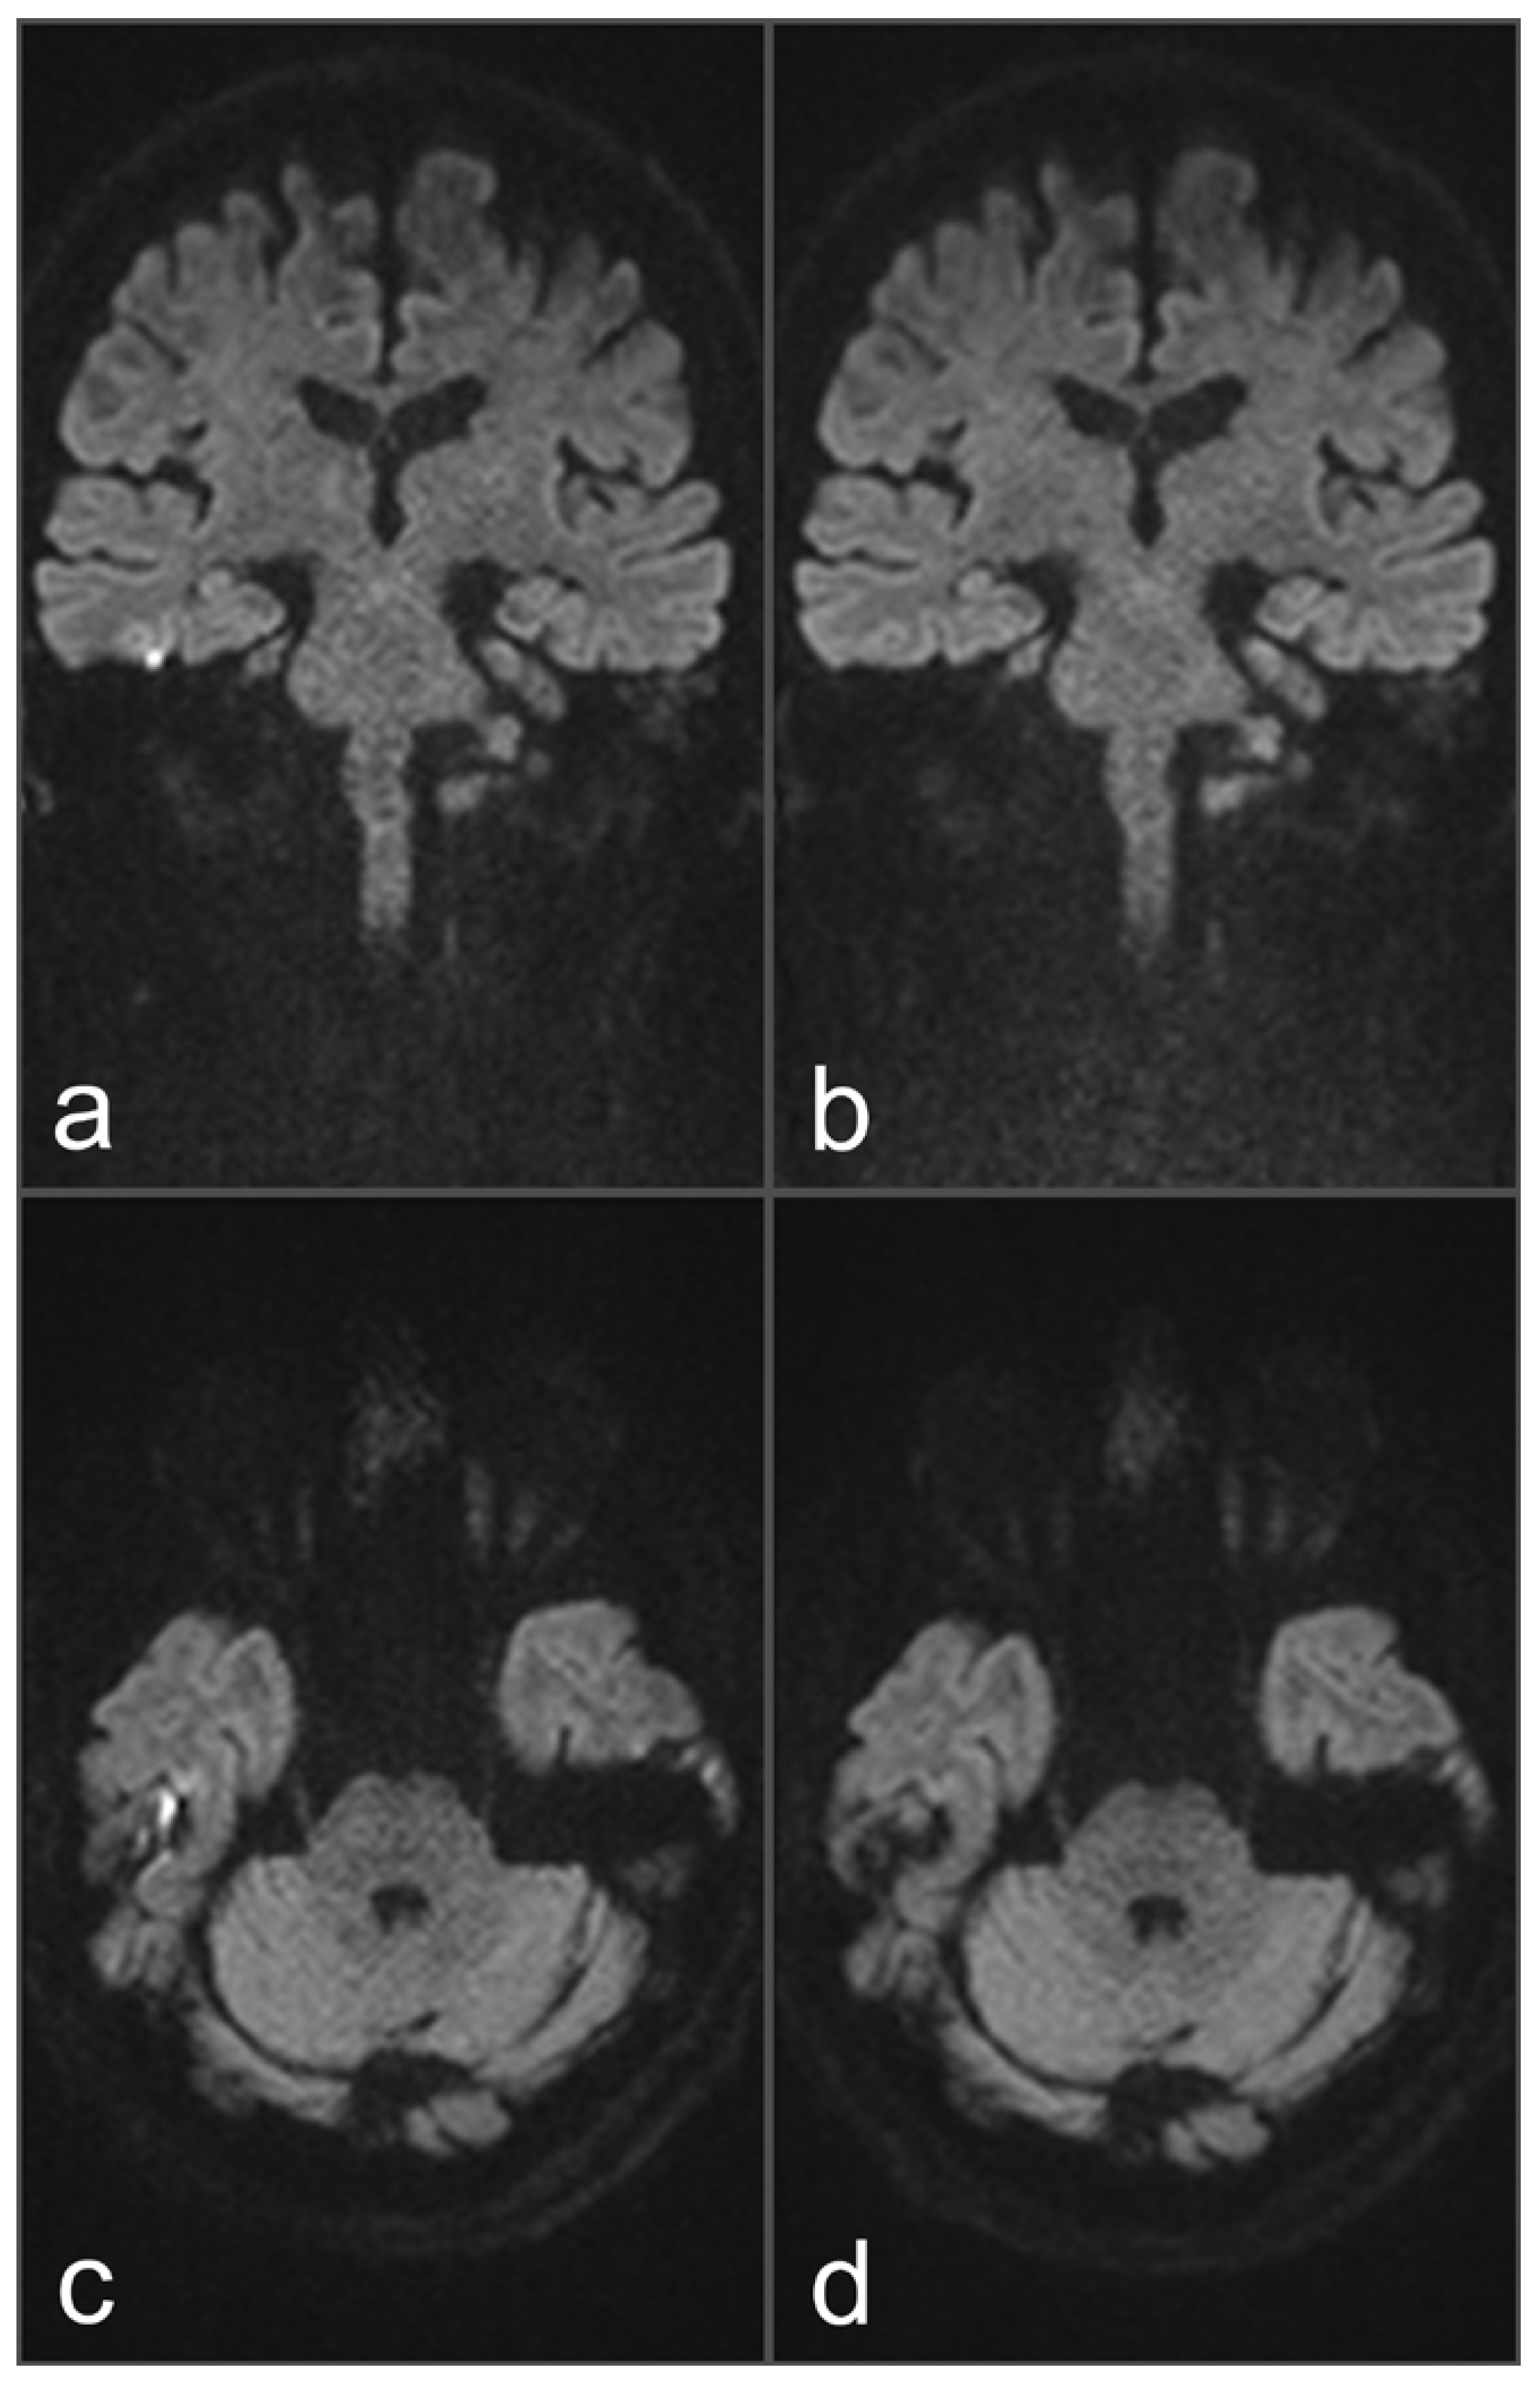

Figure 1. Images of a 34-year-old patient with a suspected cholesteatoma on the right side. (a) and (c) uncorrected rsDWI (coronal and axial slice orientation). (b) and (d) topup-corrected rsDWI (coronal and axial slice orientation). Field inhomogeneities at the height of the upper temporal bone generate a brightly appearing lesion in the uncorrected rsDWI images which might be mistaken for a cholesteatoma lesion. Notably, the lesion shows a geometrical distortion on axial slice orientation, whereas a rounded appearance could be identified on coronal image. After topup-correction, the brightly appearing lesion on the right side disappeared completely, unmasking the lesion as an artifact. The “no cholesteatoma” diagnosis was confirmed after surgery with negative histopathological proof.